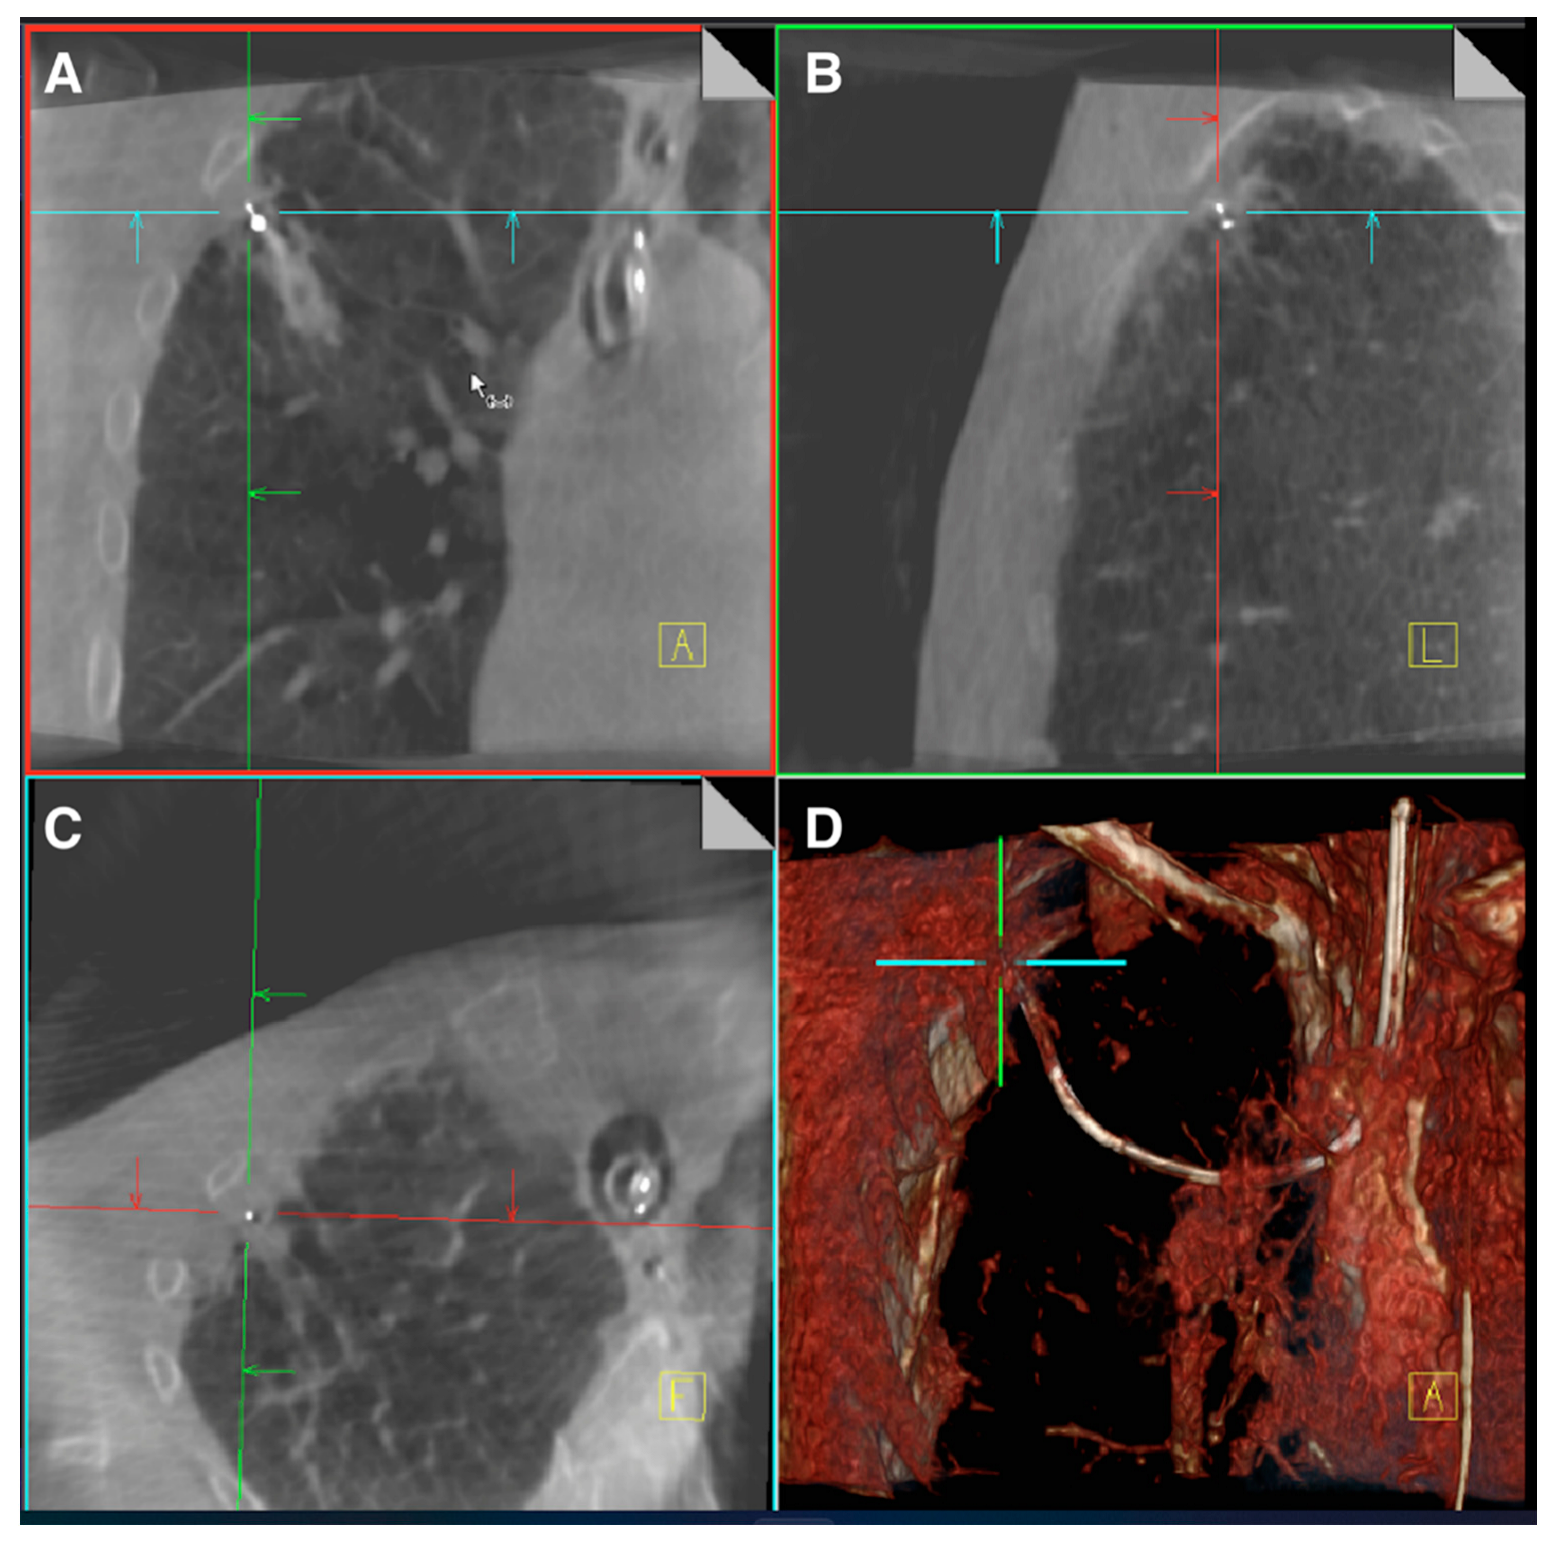

- Kalchiem-Dekel, O.; Fuentes, P.; Bott, M.J.; Beattie, J.A.; Lee, R.P.; Chawla, M.; Husta, B.C. Multiplanar 3D fluoroscopy redefines tool-lesion relationship during robotic-assisted bronchoscopy. Respirology 2021, 26, 120–123. [Google Scholar] [CrossRef]

- Reisenauer, J.; Duke, J.D.; Kern, R.; Fernandez-Bussy, S.; Edell, E. Combining Shape-Sensing Robotic Bronchoscopy with Mobile Three-Dimensional Imaging to Verify Tool-in-Lesion and Overcome Divergence: A Pilot Study. Mayo Clin. Proc. Innov. Qual. Outcomes 2022, 6, 177–185. [Google Scholar] [CrossRef]

- Sadoughi, A.; Virdi, S. Mobile 3D Intraprocedural Fluoroscopy in Combination with Ultrathin Bronchoscopy for Biopsy of Peripheral Lung Nodules. J. Bronc-Interv. Pulmonol. 2021, 28, 76–80. [Google Scholar] [CrossRef] [PubMed]